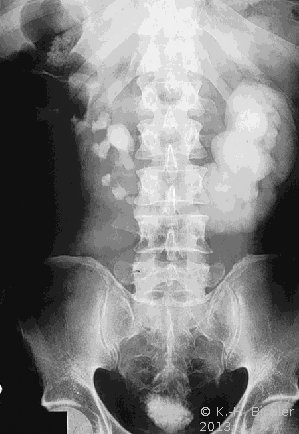

Bei einer jugendlichen Patientin kam es in Folge eines aberrierenden Gefäßes zum Harnstau im linksseitigen Hufeisennierenanteil mit Ausbildung eines fieberhaften Harnwegsinfektes. Unter der Diagnose eines aszendierenden, fieberhaften Harnwegsinfektes wurde die Patientin stationär aufgenommen, nach antibiotischer Therapie, parenteraler Flüssigkeitsapplikation und Bettruhe entfieberte die Patientin. Die Diagnostik ergab in der Sonographie einen Harnstau im linken Nierenanteil mit Verdacht auf Hufeisenniere (Abbildung 4).

Im Ausscheidungsurogramm und im CT war eine Hufeisenniere mit Pyelektasie links zu erkennen (Abbildung 5).